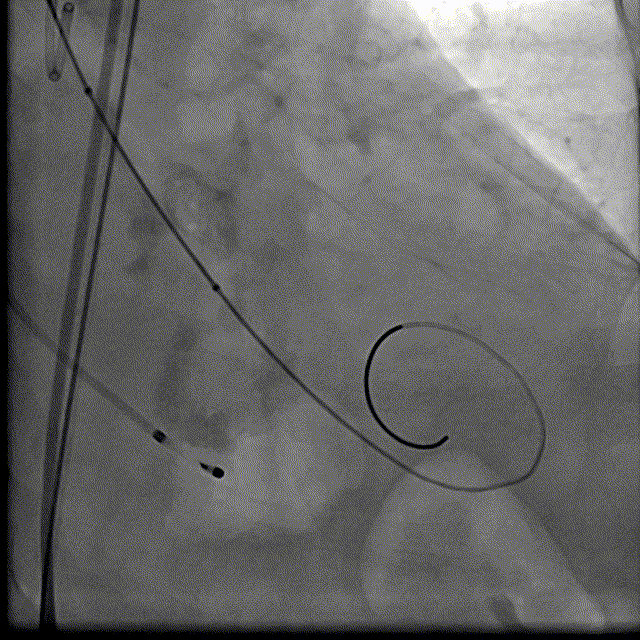

根部解刨:

手术过程